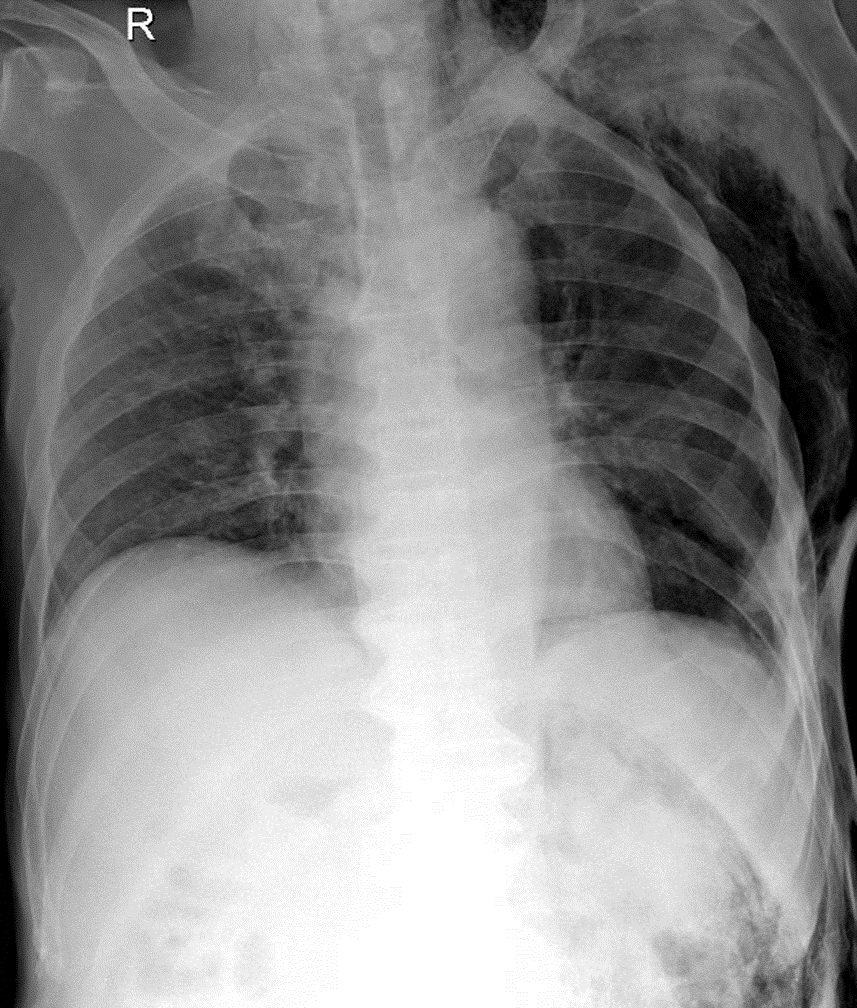

1-Tràn khí dưới da thành ngực và cổ (T) 2-Gãy cung sườn sau (T): 8, 9 3-Gãy 1/3 giữa xương đòn (T)